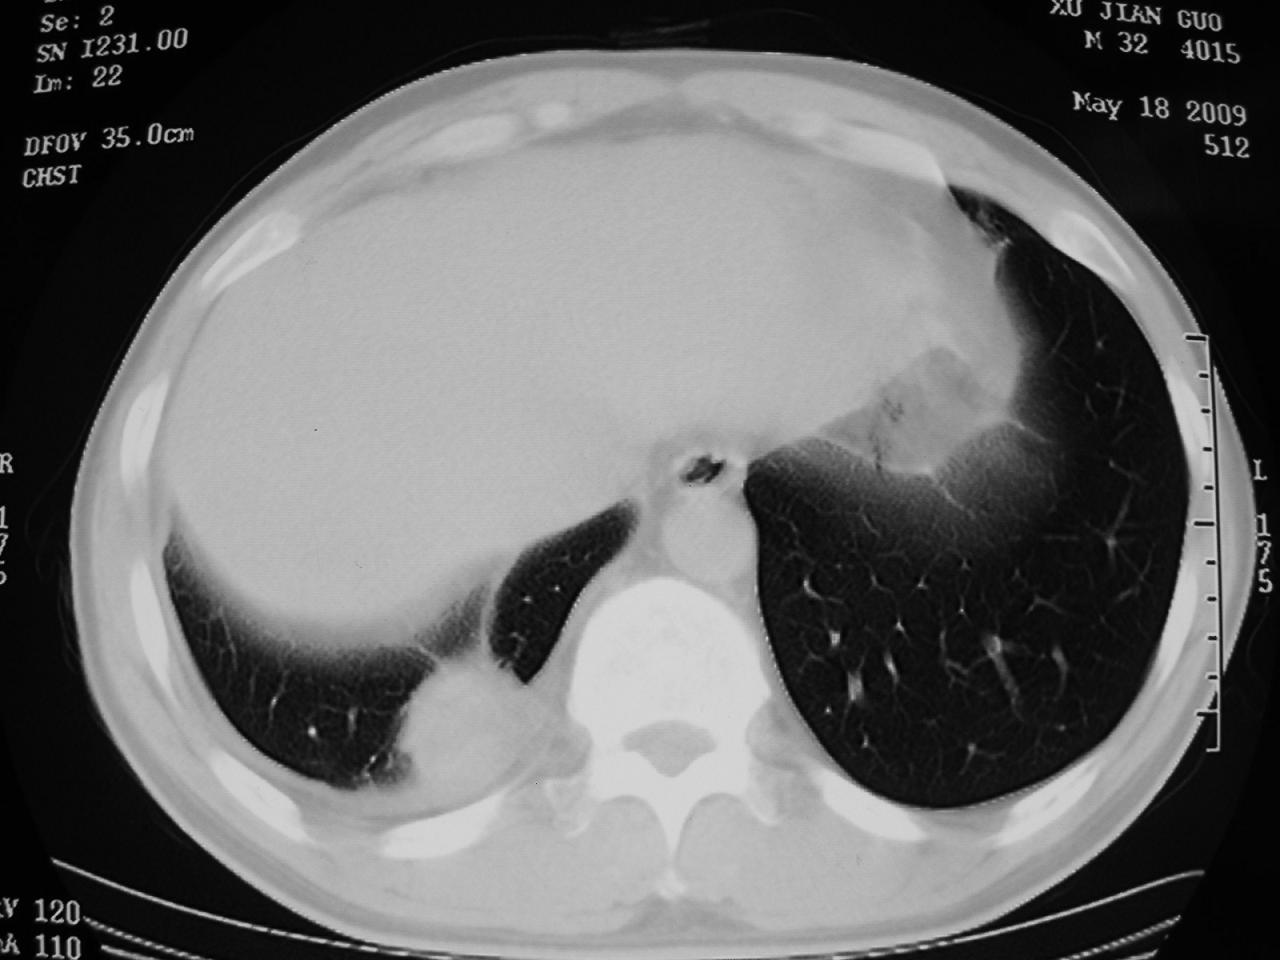

男,32岁,多年前右上肺结核,近期胸部不适,ct检查次序如上,上传主要层面,纵隔未见明显肿大淋巴结。

2009年5月18日:

本人初次(2008年12月20日ct片)诊断为右上肺结核伴右侧胸水!保守治疗后,遂复查ct胸水逐渐减少!最后(2009年05月18日)诊断为右上肺结核,右侧胸水吸收后伴包裹形成!从逐次ct检查上看,胸水吸收好转,只是从2009年05月18日ct片看到一个胸膜结节。临床医生及某肿瘤医院认为2009年05月18日ct片,右后胸壁结节,考虑为胸膜肿瘤!

本人还是倾向于右后胸壁的局限性包裹,胸膜结节密度不均匀,其内可见低密度区,考虑是由胸水吸收后胸膜增厚、粘连及周围肺组织包裹形成的征象;不倾向于胸膜肿瘤的诊断。